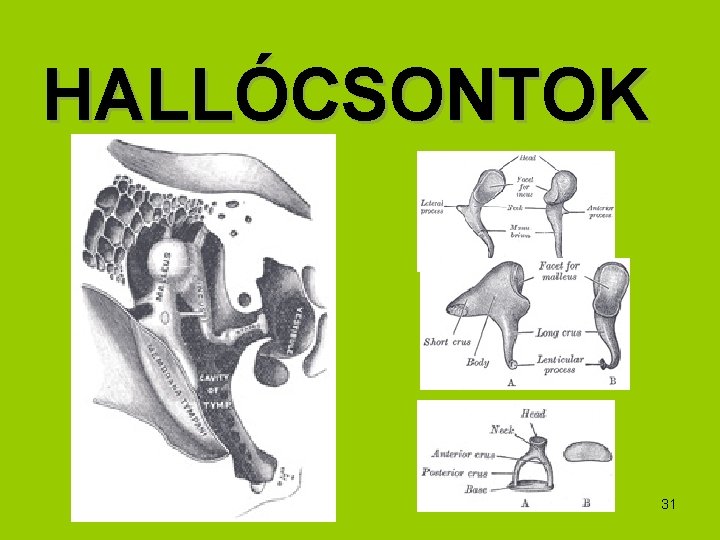

HALLÓCSONTOK 31